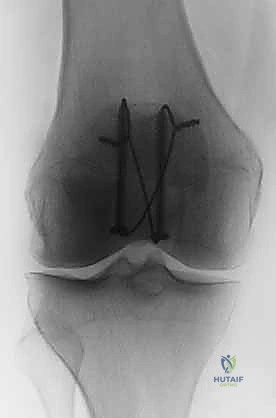

الدليل الشامل لعملية التثبيت الداخلي بالأسلاك (ORIF with Tension Band Wiring) خطوة بخطوة

تُعتبر تقنية "شريط التوتر" (Tension Band Wiring - TBW) المعيار الذهبي والأكثر استخدامًا في علاج كسور الرضفة المستعرضة. تعتمد هذه التقنية الميكانيكية العبقرية على تحويل قوى الشد (Tensile forces) التي تولدها العضلة الرباعية في الجزء الأمامي من الرضفة، إلى قوى ضغط (Compressive forces) تفيد في التئام الكسر في الجزء الخلفي (المفصلي).

إليكم تفصيل دقيق لخطوات العملية كما يجريها الخبير الأستاذ الدكتور محمد هطيف، مع التركيز على الدقة الجراحية والأمانة الطبية: